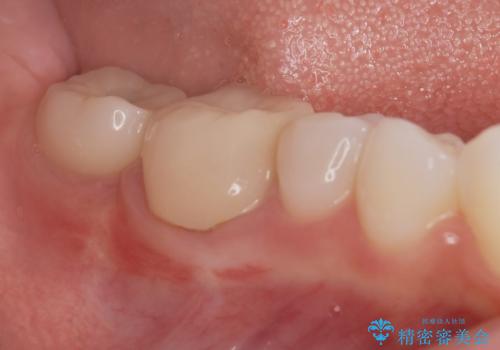

奥歯のインプラント治療

- 右下の奥歯を虫歯で喪失しそれ以来よく物が噛めず、改善を求めて来院されました。

入れ歯かインプラント治療のご提案を行い、よりしっかりとかめるインプラント治療を希望されました。

骨との結合する期間が早く、大きな咬合力にもしっかりと耐えることのできるストローマンインプラントを用いた咬合機能回復を計画します。

- 44万円(ストローマンインプラント・チタンカスタムアバットメント・仮歯・フルジルコニアクラウン)費用は治療当時の料金となります